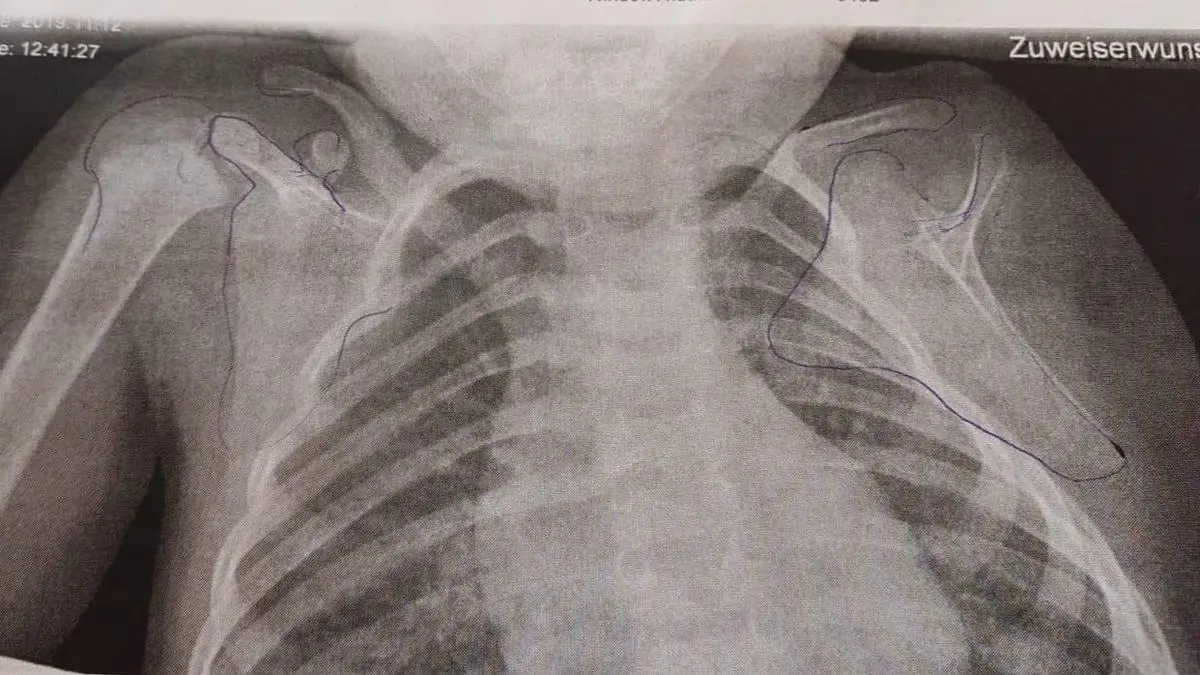

Auf dem Röntgenbild des Kindes ist die Fehlbildung an der linken Seite deutlich zu sehen